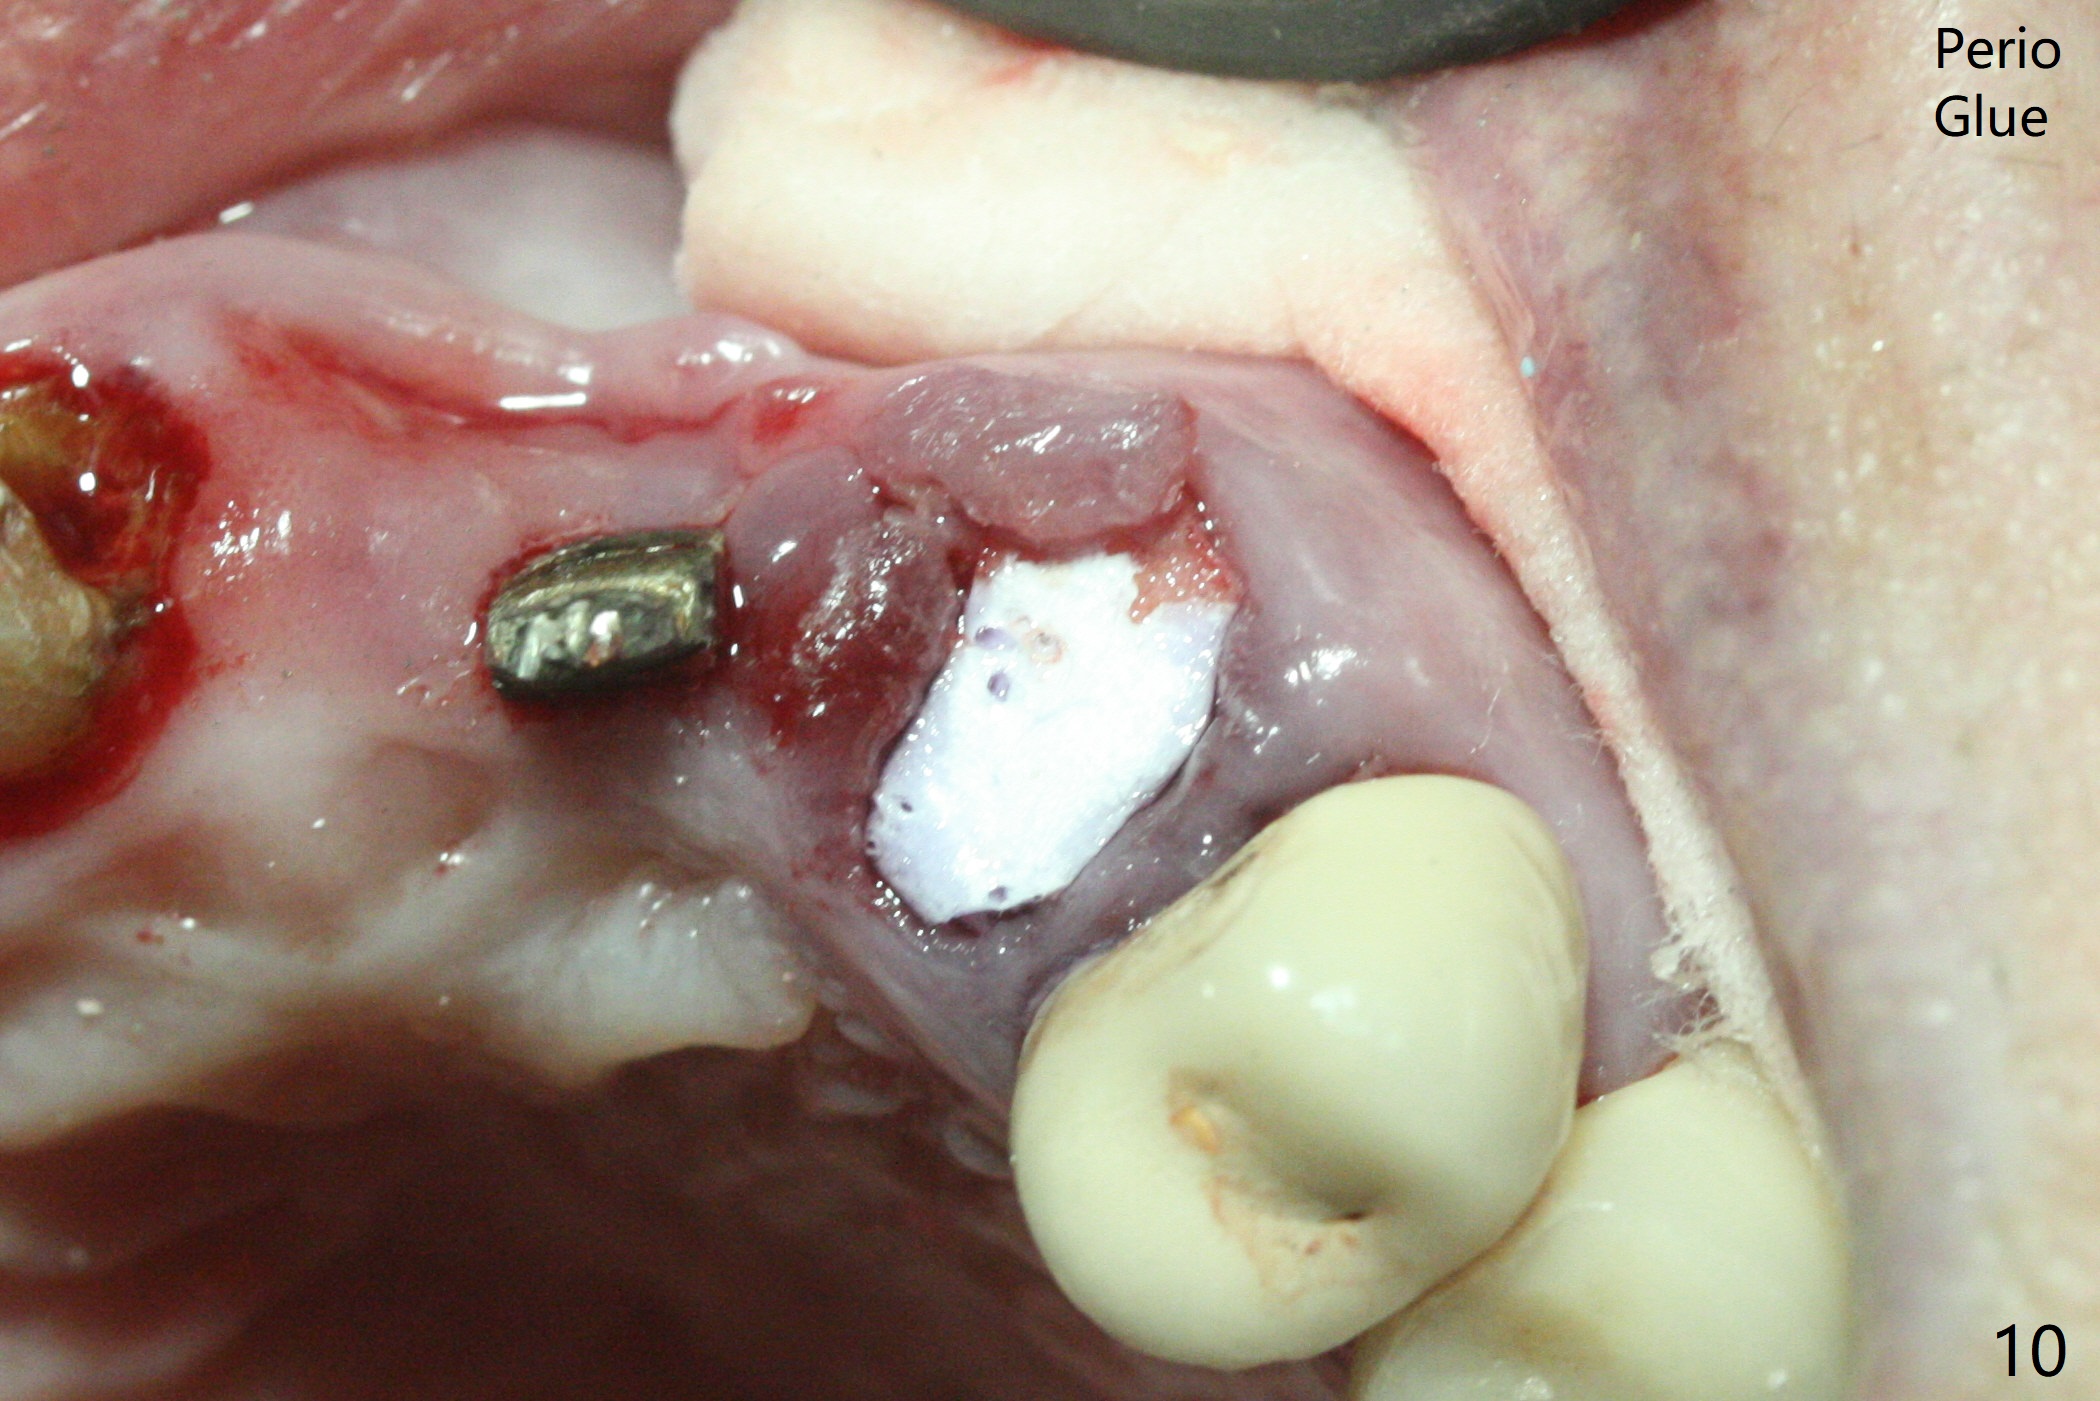

上前牙桥撤除显示右上1,2牙齿以及左上2叶片状植体好像可以保留,而左上3牙齿不能(图一,二(<:托牙边缘压迹)),拔除左上3牙齿后, 暂时把牙桥回位(图三:FPD(已经去除左上3号牙牙冠))作为3号牙种植位置参考(图四至六(G:骨粉))。其实植入前,当最后一个钻头还在原位,将PRF膜和粘性骨放置颊侧根尖(但愿骨粉能放深点),因为那里骨质很薄,好像缺损。由于植体扭力很低(大约5Ncm),放置骨粉覆盖植体(图七),为了不用缝线,涂牙周胶水(图八),放置胶原膜(图九),再涂胶水(图十)固定,最后利用右上1,2号牙(去龋,build-up后)和左上2植体制作临时牙桥,并且覆盖左上3牙槽窝。术后即刻CT显示植体颊侧(B)骨粉(图十一:*)。<:植体根尖仍有间隙,植体应该再长2毫米,初步稳定性会好些。左上3植牙愈合后,将与左上2植体制作左上1-3悬臂桥,右上1,2号牙将做根管治疗,桩,牙冠。临时牙桥术后十一天松动,右上一,二牙牙髓活性测定正常,深洗后,再次build up,不小心把左上3胶原膜吹掉,下面骨粉还稳定。术后三周病人回来做右上六种植,前牙临时修复体(图十二)需要修改(图十三)。拍摄三个方向照片显示前牙牙龈乳头(颊侧和咬合面)。